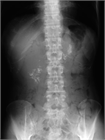

1. 膵管内の結石(膵石)を認めた場合と、膵全体に分布する複数かつびまん性の石灰化を認めた場合は慢性膵炎と診断できる(推奨度1)

1. 加齢現象に伴い膵石が観察される場合がある。